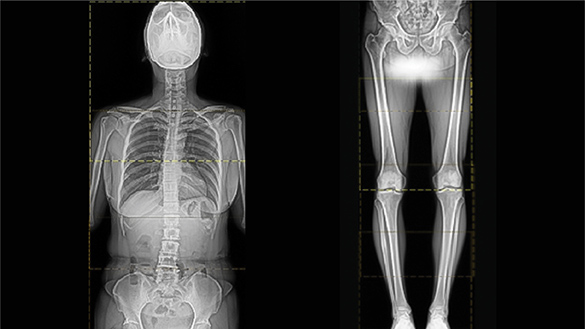

Image Stitching

RadTrainer provides a training environment for whole-spine stitching and long-bone stitching.